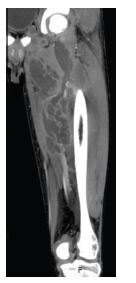

A previously healthy 16-year-old male presented to the Emergency Department with a 10-day history of edema and pain in the left upper eyelid and complaints of pain in the left thigh. He had no fever. On examination, erythema and edema with fluctuation of the left upper eyelid and frontal region were observed associated with proptosis and blurred vision. Additionally, he had edema, redness, heat and pain, and claudication in the left thigh and gluteal region. There were no signs of trauma, insect bites, or foreign bodies. The boy denied illicit drug use, namely intravenous use. Blood tests revealed leukocytosis (33,700 cells/μL) with neutrophilia (30,600 cells/μL) and elevated C-reactive protein (303 mg/L). Creatine kinase was normal. Computed tomography (CT) scan showed a multiloculated collection in the muscle planes of the thigh (Figure 1) and a partial thrombus in the left femoral vein. It also showed an expanding intraorbital lesion with proptosis and optic nerve extension (Figure 2). Empiric antibiotic therapy with ceftriaxone, clindamycin, and vancomycin was initiated, and the patient underwent surgical drainage of the intraorbital abscess and deep loculated collection in the left thigh. Methicillin-susceptible Staphylococcus aureus was isolated from blood and exudate cultures. During hospitalization, the boy remained persistently febrile despite analytical improvement. Thoracic, abdominal, and pelvic high-resolution CT scans were performed on day 8, showing bilateral cavitary lung lesions (Figure 3).

Figure 2 Cranial CT scan on admission showing an expansive intraorbital lesion on the left.